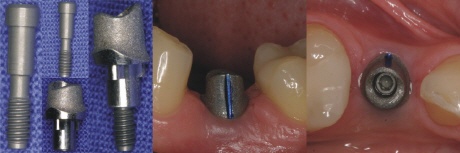

Ein Implantat besteht in der Regel aus reinem Titan und stellt ein der Zahnmedizin den künstlichen Ersatz einer natürlichen Zahnwurzel dar.

Auf das schraubenförmige Implantat wird mit einer Schraube ein Aufbau (Pfosten) geschraubt. Dieser bietet die Basis für den Zahnersatz. Auf den Aufbau wird beispielsweise eine Krone, eine Brücke oder auch andere Halteelemente, wie zum Beispiel ein Teleskop, aufzementiert.

1. Das Implantat

Das Implantat ist der künstliche Ersatz der natürlichen Zahnwurzel

2. Der Aufbau

Auf dieses Implantat wird ein so genannter Aufbau aufgeschraubt. Dieser bekommt seinen Halt über eine spezielle Innenverbindung, oder in seltenen Fällen über eine Außenverbindung. Diese Verbindung bietet den Rotationsschutz des Aufbaus und der Krone.

3. Die Suprakonstruktion

Die Suprakonstruktion (Krone) ist letztlich das einzige, was später noch im Mund zu sehen ist. Sie wird auf den Aufbau festzementiert oder aber mit dem Aufbau verschraubt.